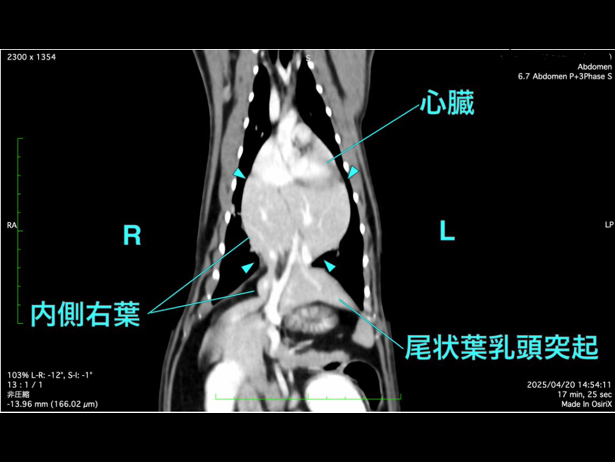

詳しく調べるためにCT検査を行った結果、「腹膜心膜横隔膜ヘルニア」と診断されました。

CT検査にて手術前評価